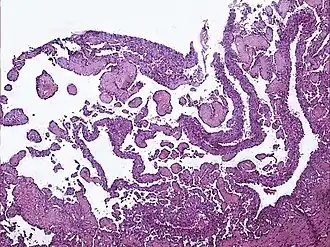

Guz Dąbskiej (łac. angioendothelioma papillare endovasculare malignum, ang. Dabska tumor, malignant endovascular papillary angioendothelioma) – rzadki nowotwór tkanek miękkich o małym potencjale złośliwości, spotykany głównie u dzieci. Guz lokalizuje się zazwyczaj na kończynach, rzadziej w obrębie głowy albo szyi lub w innych lokalizacjach (np. jądro[1]); może przyjmować postać ograniczoną do skóry albo rozlaną, zajmując też tkankę podskórną. W obrazie histologicznym stwierdza się przestrzenie naczyniowe z brodawkowymi tworami i naciekiem limfocytów w podścielisku[2]. Leczenie polega na chirurgicznej resekcji z szerokim marginesem zdrowych tkanek. Nazwa guza honoruje polską patomorfolog Marię Dąbską, która opisała pierwszy przypadek tego nowotworu w 1969 roku[3].